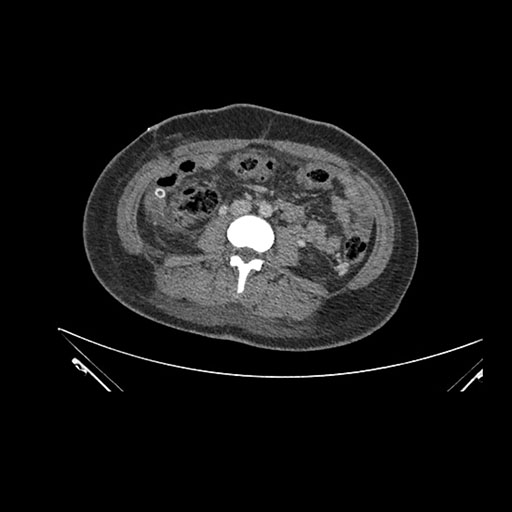

Imaging Analysis

Look through the patient's CT scan to identify any areas of concern for the necessary procedure.

Axial Arterial

Based on initial findings, which issue(s) would you be most concerned about?